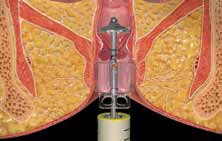

Απαιτείται συχνότερα σε χολολιθίαση : δηλαδή παρουσία λίθων εντός της χοληδόχου κύστεως.

Χολοκυστεκτομή (αφαίρεση χοληδόχου κύστεως)Η διάγνωση συνήθως γίνεται με ένα απλό υπερηχογράφημα.Η χολολιθίαση...